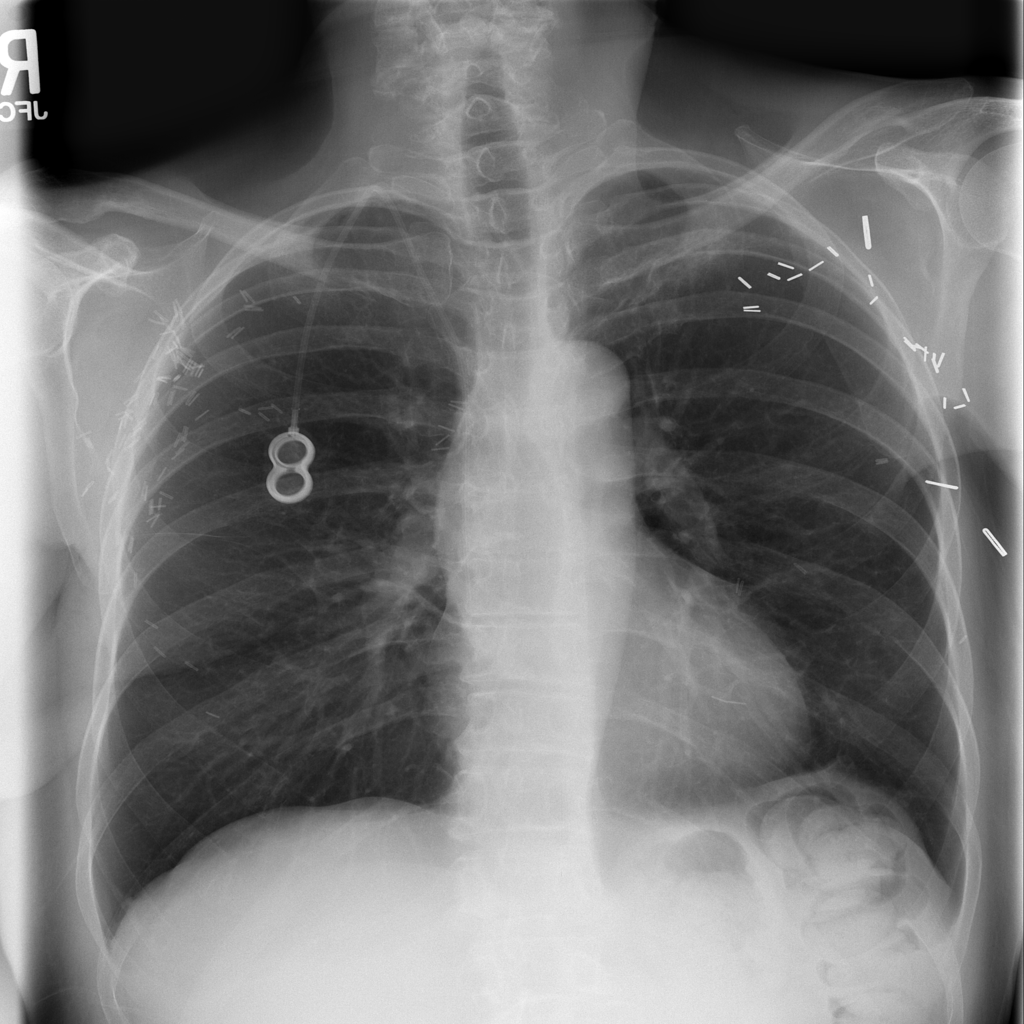

PAT-86C8 · IMG-006Atelectasis

PAT-86C8 · IMG-006

PA